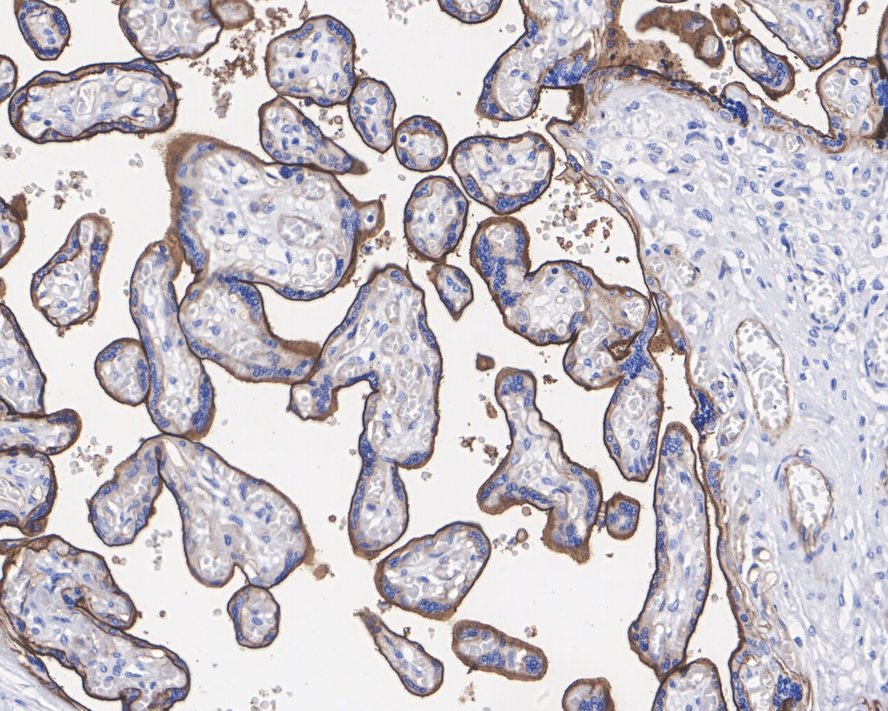

Immunohistochemical analysis of paraffin-embedded human placenta tissue with Rabbit anti-CD200 antibody (HA721691) at 1/2,000 dilution.

The section was pre-treated using heat mediated antigen retrieval with Tris-EDTA buffer (pH 9.0) for 20 minutes. The tissues were blocked in 1% BSA for 20 minutes at room temperature, washed with ddH2O and PBS, and then probed with the primary antibody (HA721691) at 1/2,000 dilution for 1 hour at room temperature. The detection was performed using an HRP conjugated compact polymer system. DAB was used as the chromogen. Tissues were counterstained with hematoxylin and mounted with DPX.